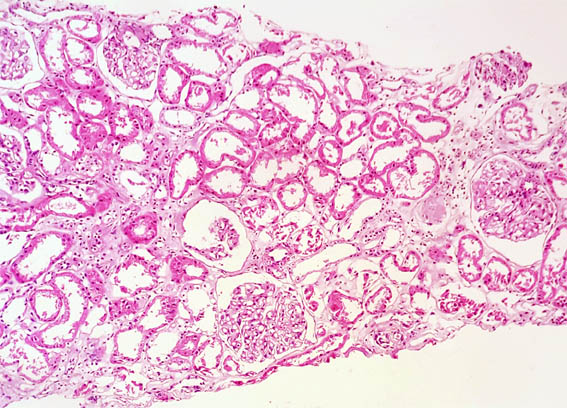

Clinical information

See the images of the renal biopsy.

Figure 1. H&E, X100.